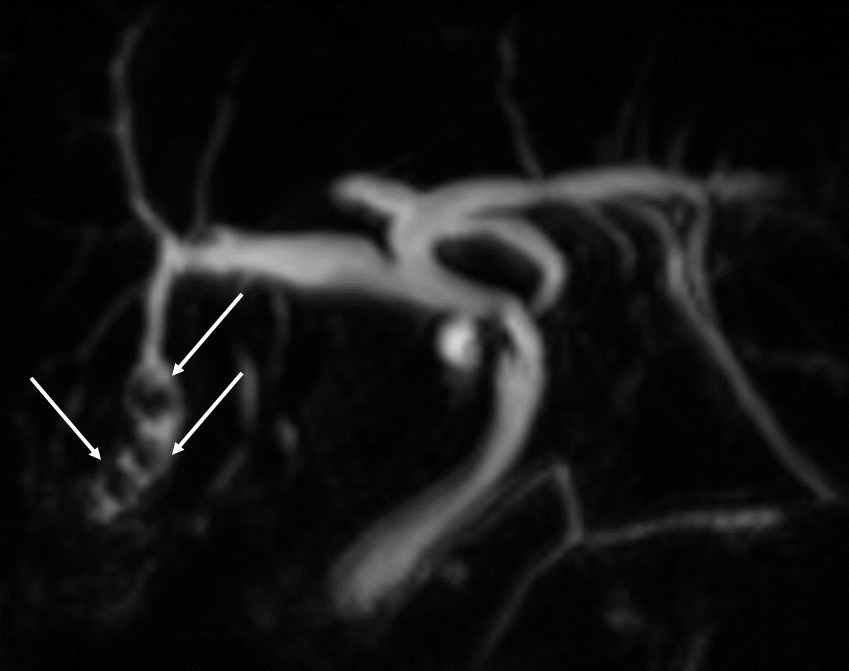

La cholangiographie par IRM est typiquement normale dans les formes habituelles, microlithiasiques, du syndrome LPAC. Elle n’est donc pas nécessaire au diagnostic dans la très grande majorité des situations. Elle doit être réalisée en cas de calculs intrahépatiques ou de dilatation des canaux biliaires en échographie afin d’évaluer le retentissement de ces calculs sur les voies biliaires et le parenchyme hépatique. Les calculs biliaires ne sont pas toujours visibles à l’imagerie par résonance magnétique (IRM), notamment quand leur taille est inférieure à 5 mm. Lorsqu’ils sont visibles, ils sont le plus souvent visualisés en hyposignal T1 et T2 sous forme de lacunes endobiliaires (fig. 2 A et 2B). Dans une série récente portant sur 125 patients suivis dans un centre expert et ayant tous eu une bili-IRM, 49 % présentaient des anomalies des canaux biliaires, parmi lesquelles 93 % de calculs intra­hépatiques et 38 % de dilatation des canaux biliaires.10 Ces anomalies morphologiques étaient plus fréquemment observées chez les porteurs d’un variant pathogène du gène ABCB4.